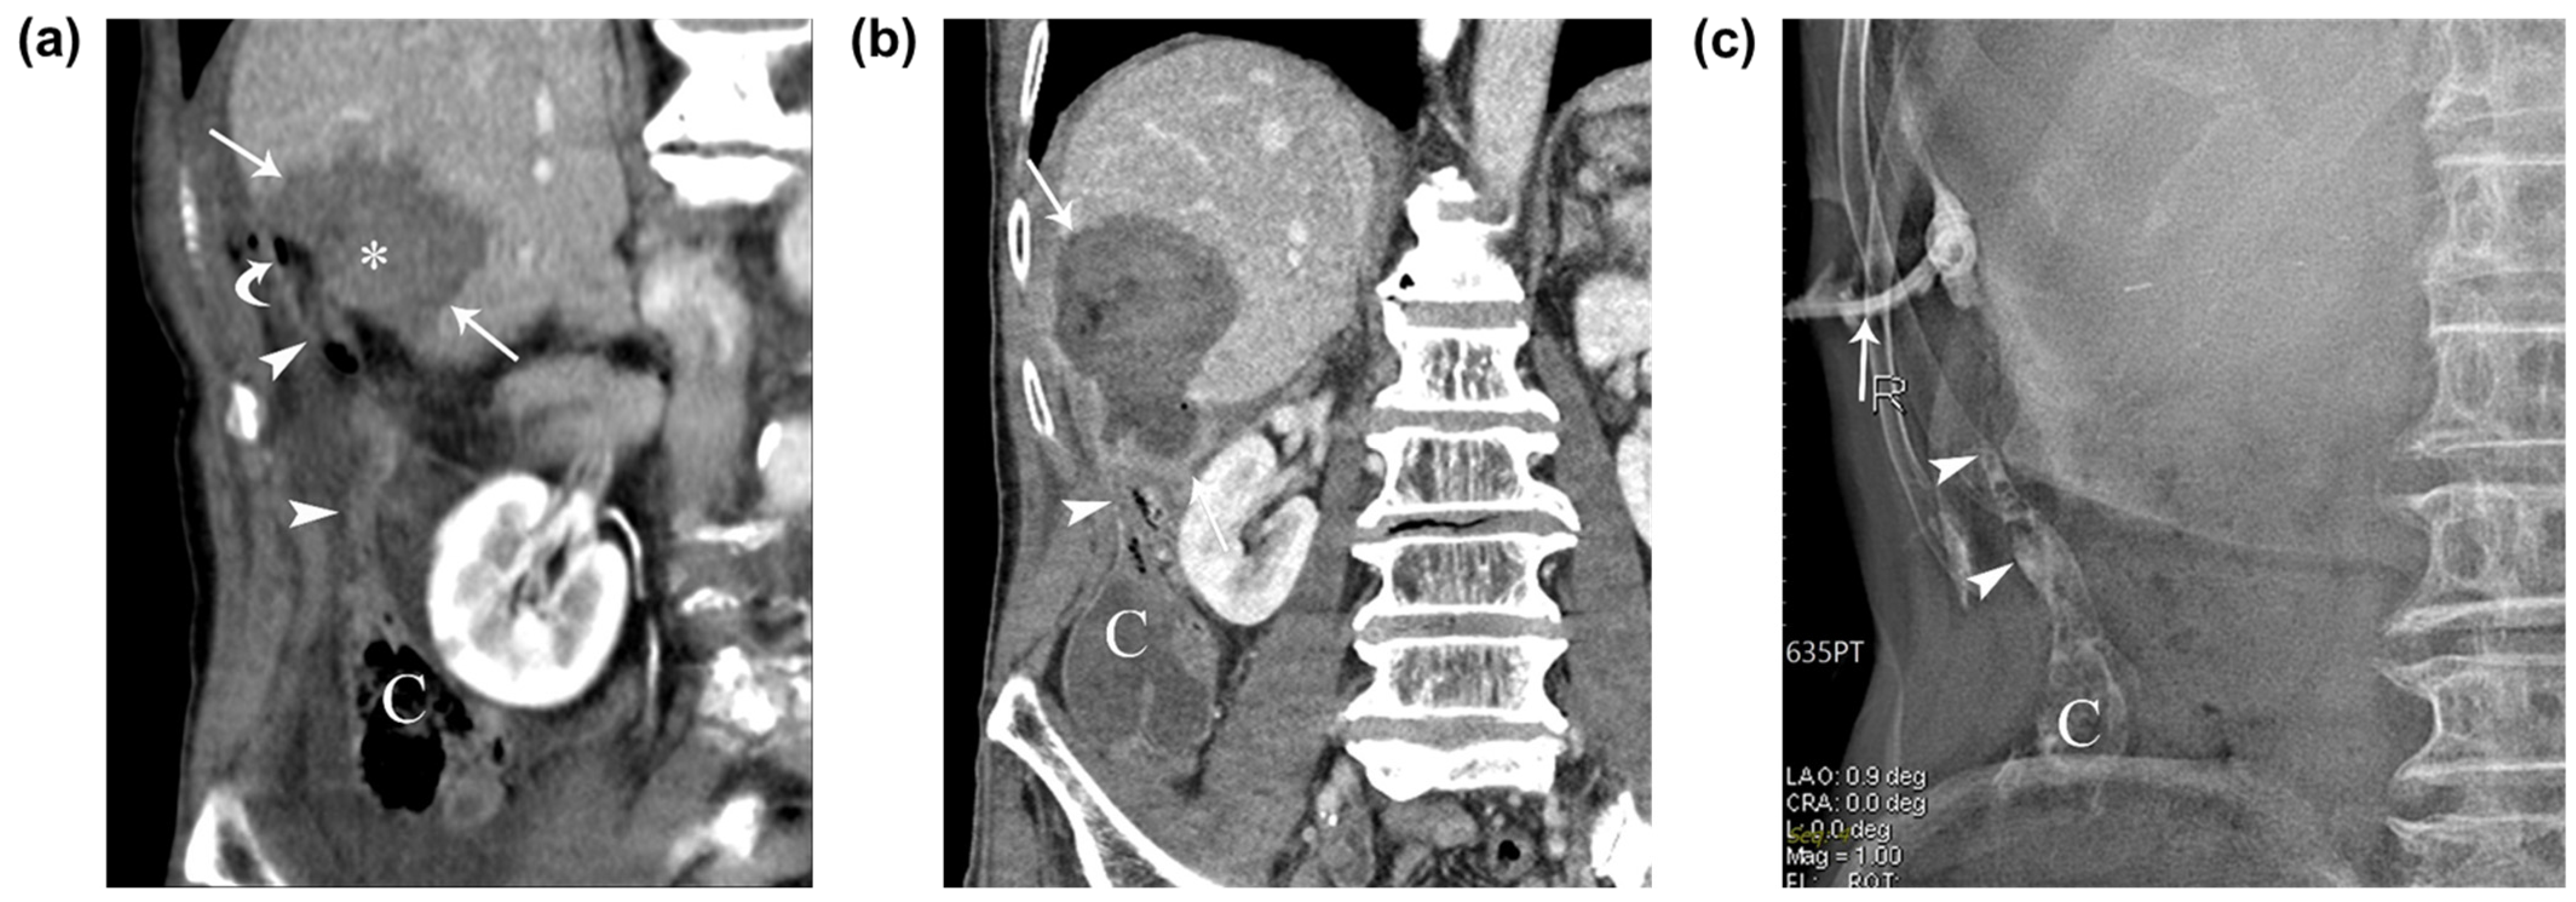

An immediate post-RFA contrast-enhanced CT scan demonstrated a low-attenuating ablated area that covered the tumor and the air-filled appendix, which extended superiorly from the cecum to the perihepatic space near the ablated zone of segment 5 of the liver, with a thickened appendiceal tip (Figure 2a). The patient was closely monitored and treated with intravenous antibiotics. On the fifth day after RFA, the patient’s laboratory results showed elevated aspartate aminotransferase and alanine aminotransferase levels, as well as an elevated high-sensitive C-reactive protein level. The patient presented with intermittent right upper abdominal pain and chills after the RFA, and a follow-up CT scan performed 7 days later revealed the formation of an abscess in the ablated zone and adjacent perihepatic space, although communication between the appendix and the ablated zone was not clear on the CT scan. A 10-French pigtail percutaneous drainage catheter was inserted into the hepatic abscess between the ablated zone and the perihepatic appendix (Figure 2b), and fluoroscopic imaging showed a fistulous tract between the ablated zone and appendix (Figure 2c). Abscess formation after percutaneous ultrasound-guided radiofrequency ablation for a 1.2 cm subcapsular hepatocellular carcinoma in segment 5 of the liver. (a) Immediate follow-up contrast-enhanced coronal CT image after ultrasound-guided radiofrequency ablation depicts a low-attenuating ablated area (arrows) which sufficiently covers the tumor (asterisk) and an air-filled perihepatic appendix (arrowheads) with a thickened tip from cecum (C). Note the small air density (curved arrow) between the ablated area and the appendiceal tip. (b) Follow-up contrast-enhanced coronal CT image taken 7 days after the RFA depicts abscess formation in the ablated zone and adjacent perihepatic space (arrow) and a thickened perihepatic appendix (arrowheads). (c) A 10-French pigtail percutaneous drainage catheter (arrow) was inserted into the sinus between the ablated area and the appendiceal tip. The fluoroscopic image depicts the contrast-filled appendix (arrowheads) with mottled air density and cecum (C). After 1 month, the patient’s clinical symptoms and laboratory findings subsided and improved, and a follow-up tubogram showed an improving abscess with a remaining fistula. Surgical treatment was initially considered, and the potential difficulties due to postoperative adhesion and potential postoperative complications were explained to the patient. However, the patient opted against this approach, leading us to decide on a conservative treatment. The patient was discharged following the removal of the percutaneous drainage catheter.